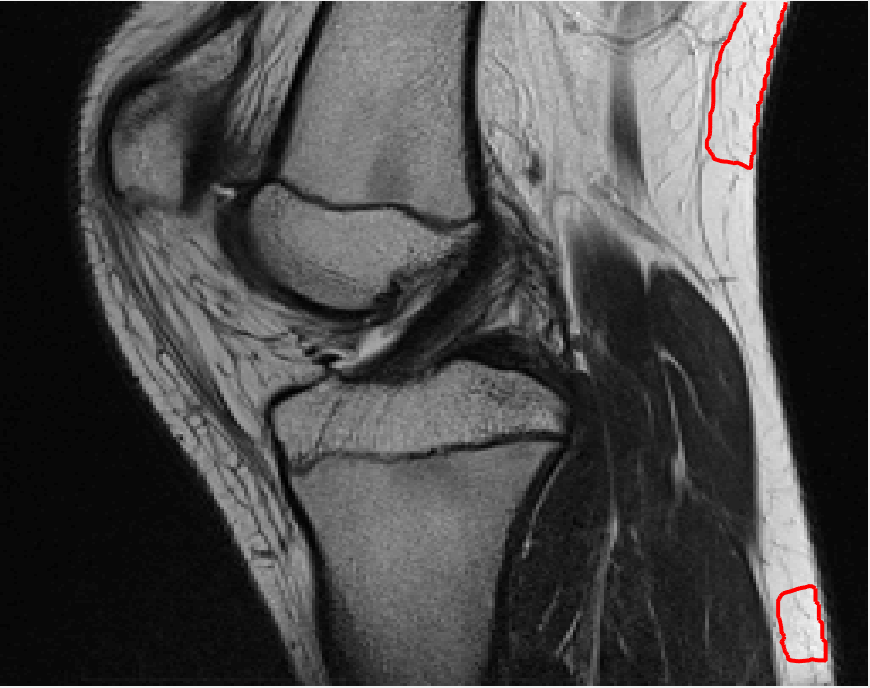

Four sets of test results are shown below. In Test 1 we compare models M1 – M6 to the proposed model M7 for two images which are hard to segment. The first is a CT scan from which we would like to segment the lower portion of the heart, the second is an MRI scan of a knee and we would like to segment the top of the Tibia. See Figure 9 for the test images and the marker sets used in the experiments. In Test 2 we will review the sensitivity of the proposed model to the main parameters. In Test 3 we will give several results achieved by the model using marker and anti-marker sets. In Test 4 we show the initialisation independence and marker independence of the Geodesic Model on real images.

In this test we give the segmentation results for models M1 – M7 for the two challenging test images shown in Figure 9. The marker and anti-marker sets used in the experiments are also shown in this figure. After extensive parameter tuning, the best final segmentation results for each of the models are shown in Figures 10 and 11. For M1 – M4 we obtain incorrect segmentations in both cases. In particular, the results of M2 and M4 are interesting as the former gives poor results for both images, and the latter gives a reasonable result for Test Image 1 and a poor result for Test Image 2. In the case of M2, the regularisation term includes the edge detector and the distance penalty term (see (4)). It is precisely this which permits the poor result in Figures 10(b) and 11(b) as the edge detector is zero along the contour and the fitting terms are satisfied there (both intensity and area constraints) – the distance term is not large enough to counteract the effect of these. In the case of M4, the distance term and edge detector are separated from the regulariser and are used to weight the Chan-Vese fitting terms (see (9)). The poor segmentation in Figure 11(b) is due to the Chan-Vese terms encouraging segmentation of bright objects (in this case), weighting enforces these terms at all edges in the image and near . In experiments, we find that M4 performs well when the object to segment is of approximately the highest or lowest intensity in the image, however when this is not the case, results tend to be poor. We see that, in both cases, models M5 and M6 give much improved results to M2 and M4 (obtained by incorporating the geodesic distance penalty into each). The proposed Geodesic Model M7 gives an accurate segmentation in both cases. It remains to compare M5, M6 and M7. We see that M5 is a non-convex model (and cannot be made convex [39]), therefore results are initialisation dependent. It also requires one more parameter than M6 and M7, and an accurate set to give a reasonable area constraint in (4). These limitations lead us to conclude M6 and M7 are better choices than M5. In the case of M6, it has the same number of parameters as M7 and gives good results. M6 can be viewed as the model M7 with weighted intensity fitting terms (compare (18) and (30)). Experimentally, we find that the same quality of segmentation result can be achieved with both models generally, however M6 is more parameter sensitive than M7. This can be seen in the parameter map in Figure 12 with M7 giving an accurate result for a wider range of parameters than M6. To show the improvement of M7 over previous models, we also give an image in Figure 13 which can be accurately segmented with M7 but the correct result is never achieved with M6 (or M3). Therefore we find that M7 outperforms all other models tested M1 – M6.